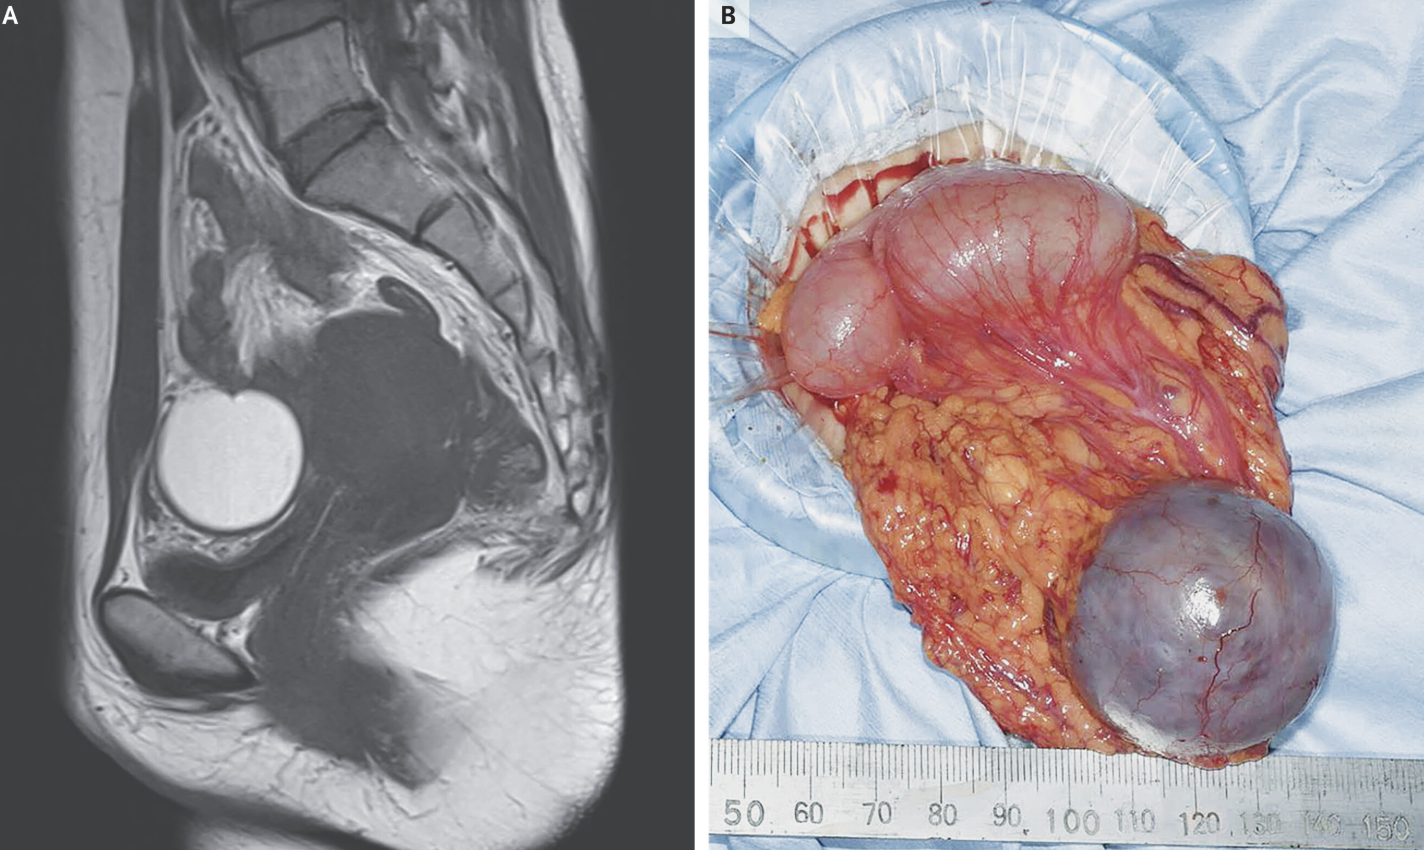

Things That Could Have Been Brought To My Attention Yesterday! Gallery Things That Could Have Been Brought To My Attention Yesterday! By Nicole Angemi|2025-02-23T10:59:55-05:00February 23rd, 2025|Pregnancy, Congenital Anomaly, Women's Health, The Gross Room, MEDICAL| Read More 18